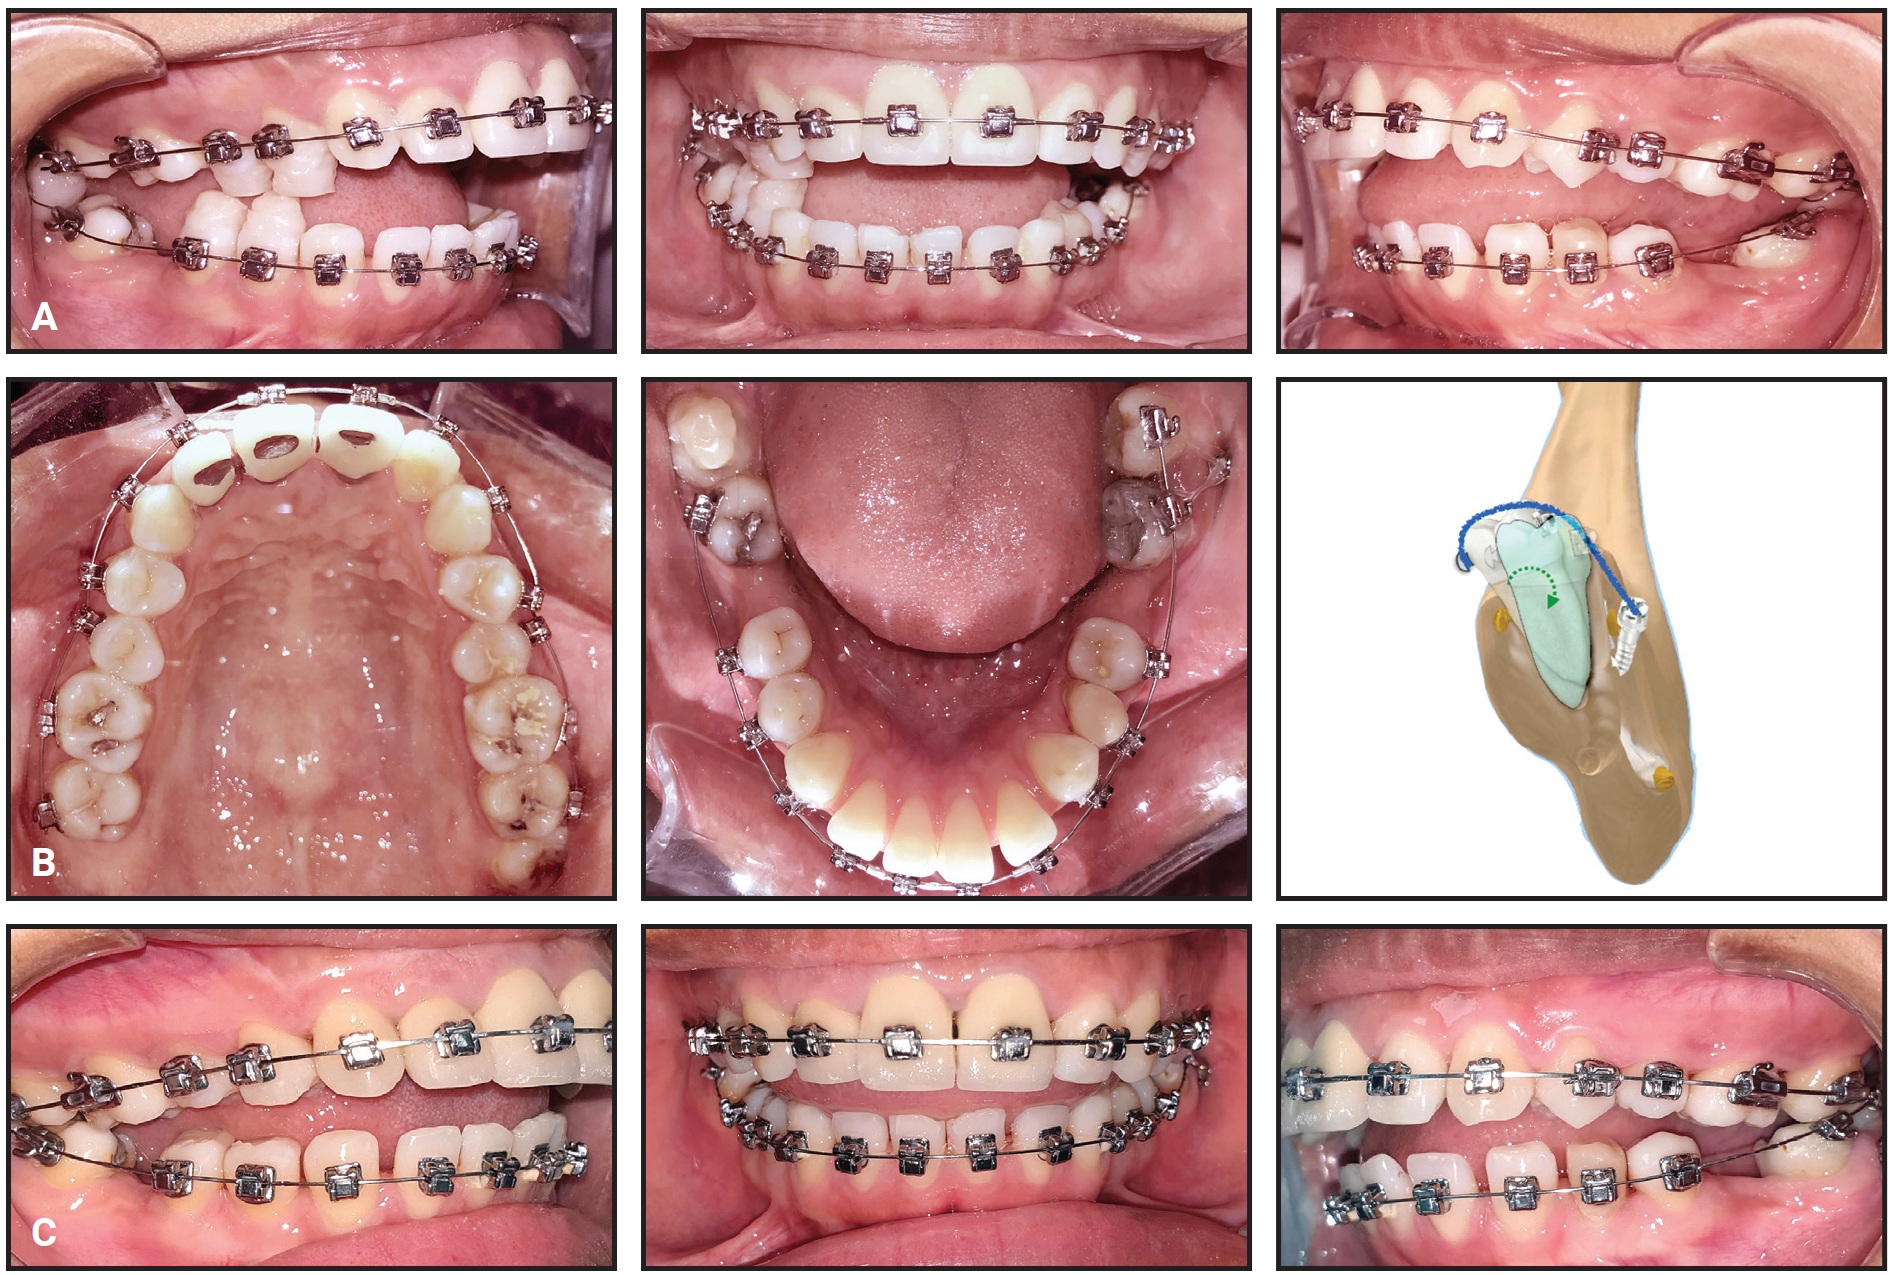

Total treatment time was 22 months (Fig. 11). The patient’s facial profile was more convex and esthetically pleasant. The dental midlines appeared centered in smiling, the black corridors were significantly reduced, and the smile arc was consonant. The incisor display was improved, although a slight asymmetry in gingival exposure could be observed in smiling. Bilateral Class I canine and molar relationships were obtained and the open bite was corrected, with ideal overbite and optimal alignment in both arches. A slightly uneven gingival margin at the upper right canine was attributable both to the initial cant of the maxillary occlusal plane and to a need for further bracket repositioning or wirebending in the finishing phase.

Fig. 11 A. Patient after 22 months of treatment. B. Superimposition of pretreatment (black) and post-treatment (red) cephalometric tracings.

The final panoramic radiograph showed good root parallelism and proper leveling of the interdental bone peaks, with no signs of root resorption. Cephalometric analysis (Table 1) confirmed an improvement in the skeletal sagittal discrepancy (ANB = 1.7°, Wits appraisal = –3.4mm), with an increased SNA angle (78.9°) and normalized lower-incisor inclination (IMPA = 92.5°). The vertical dimension was slightly increased (FMA = 29.8°, MP-SN = 39°), owing to clockwise rotation of the mandible. Regional superimpositions showed extrusion of the upper and lower molars and incisors, but the upper-molar extrusion was more limited than the upper-incisor extrusion, indicating that a clockwise rotation of the maxillary plane had compensated for the clockwise rotation of the mandible.

After debonding, vacuformed maxillary and mandibular retainers were delivered for six months of full-time wear, followed by nighttime-only wear. To further improve vertical stability and tongue function, the patient was referred for speech therapy.

In our 14-year-old female patient, we decided to use an h-RPE with only a single phase of expansion (32 days) and concurrent facemask protraction. Stable skeletal anchorage, ensured by accurate miniscrew-insertion planning, allowed us to limit dentoalveolar effects such as mesialization of the upper first molars while maximizing the skeletal effect. Without the use of an Alt-RAMEC protocol to enhance the responsiveness of the maxilla, the orthopedic phase produced forward and downward maxillary displacement (SNA +2.1°, A-Na perp +1.7mm). Subsequent advancement of point A and retraction of pogonion (Pg-Na perp –3.2mm) were attributable primarily to clockwise rotation of the mandible (FMA +2.4°). This facemask-induced rotation could be identified as mandibular backward rotation type 2, as described by Björk, considering that a slight backward and upward growth of the condyles was observed.36 The increased vertical dimension and reduced chin projection improved the patient’s Class III facial profile. An orthodontic phase of fixed appliances and Class III elastics compensated for the mandibular rotation by extruding the anterior teeth, thus preventing the development of anterior open bite.